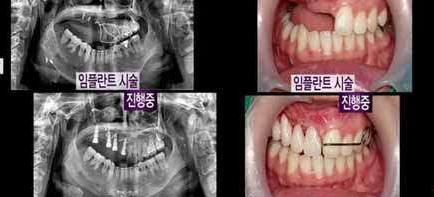

▼牙齒也無法正常生長。

▼因為表佳熙的臉嚴重歪斜,只能盡力把她畸形的部分變正常。

▼由於表佳熙已經失去右眼,因此醫生使用義眼來幫她補上眼睛。

▼原本歪斜的下巴也回到原位。

▼原本長不出的牙齒被假牙填滿。